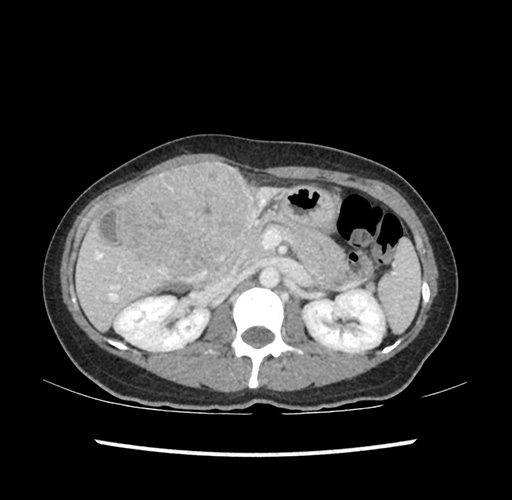

Imaging Analysis

Look through the patient's CT scan to identify any areas of concern for the necessary procedure.

Based on your CT findings, which issue(s) would give reason for "planned slowing down moment(s)" in this case?

Considering a standard left lateral sectionectomy procedure, what step(s) of the operation would you do differently in this case ?